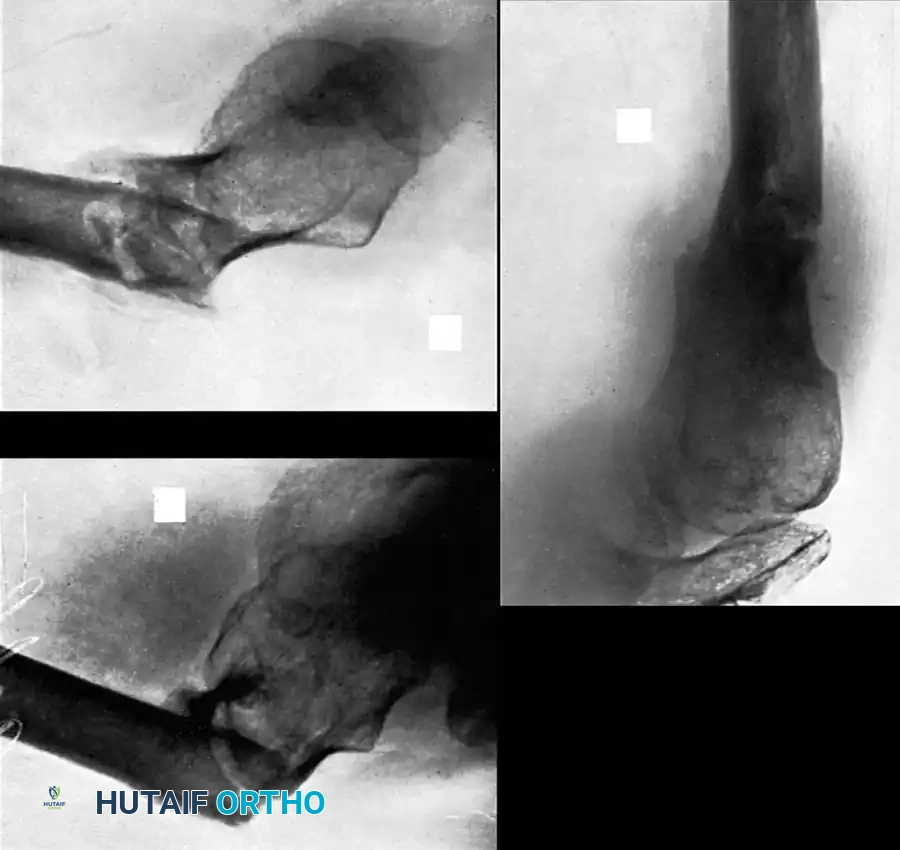

Osteotomy and Reduction

Executing the Osteotomy: Use a combination of sharp osteotomes and a microsagittal saw to recreate the original fracture line.

Surgical Warning: The saw must be cooled continually with saline irrigation to prevent thermal necrosis of the bone. Place a malleable retractor deep to the clavicle to protect the subclavian vessels and brachial plexus.

Fig. 55-25E: Osteotomy performed with a microsagittal saw. -

Mobilization: Hold the proximal and distal fragments with reduction forceps (e.g., pointed Weber clamps). Realign the clavicle. Use as little soft-tissue stripping as possible to preserve the periosteal blood supply.

Fig. 55-25F: Initial mobilization of the fragments. -

Canal Preparation: Reestablish the medullary canal using a 3.5-mm drill bit in both the proximal and distal fragments to encourage endosteal bleeding and osteogenesis.

Fig. 55-25G: Realigning the fragments to restore length. -

Correcting Malrotation: Rotate the distal fragment anteriorly so that its flat superior surface faces anteriorly rather than superiorly. Redirect the flat superior surface of the distal fragment to match the proximal segment, creating congruent surfaces.

Pitfall: Make absolutely no attempt to explore or decompress the brachial plexus deep to the clavicle during this maneuver, as the altered anatomy places these structures at high risk of iatrogenic injury.

Fig. 55-25H: Final anatomical reduction achieved.

Associated Surgical & Radiographic Imaging